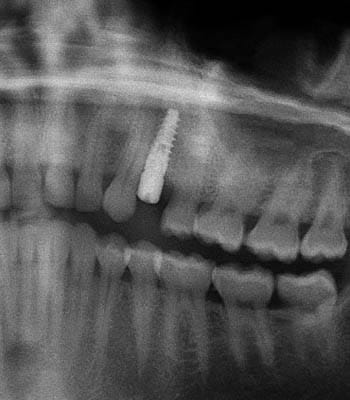

Dental implants are a titanium "root" which can be placed into the jawbone. Once integrated with your bone, the implant can be used to support a crown, a bridge, or secure a complete denture. Dental implants may be used to eliminate partial plates and dentures. The success rates for dental implants are extremely high which is due in part to the fact that root-form implants are made of a biocompatible material, titanium.

Single Tooth Replacement